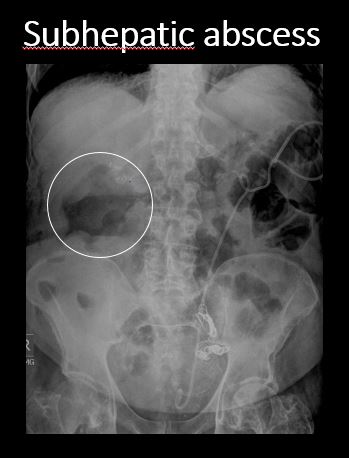

There is scattered extraluminal air or an abnormal focal collection of air in the abdomen or pelvis. [Yes/No]